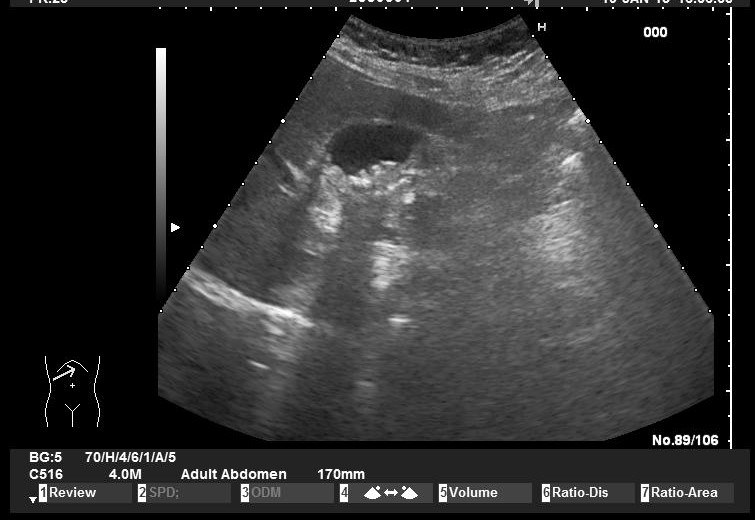

Case courtesy of Prof Adrian Saftoiu